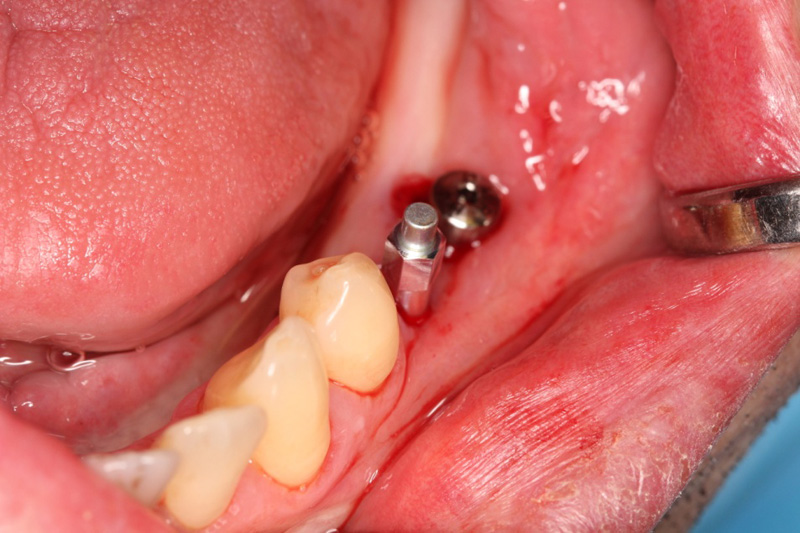

V některých případech, kdy má pacient dostatek kosti a není potřeba provádět např. její doplnění (viz

Augmentace), je možné zavádět implantáty tzv. metodou

Flapless - tedy bez nutnosti odklápět sliznici. Operace je v těchto případech šetrnější.

Tím máme všechny potřebné údaje pro plánování pozic implantátů, jejich potřebné délce a průměru. Abychom mohli implantáty zavést do naplánovaných pozic v ústech pacienta, umožňuje tento program vymodelovat speciální operační šablonu, která je zhotovena 3D tiskárnou. Pomocí této šablony, která se umístí do úst pacienta, pak probíhá vlastní operace

- zavádění implantátů.